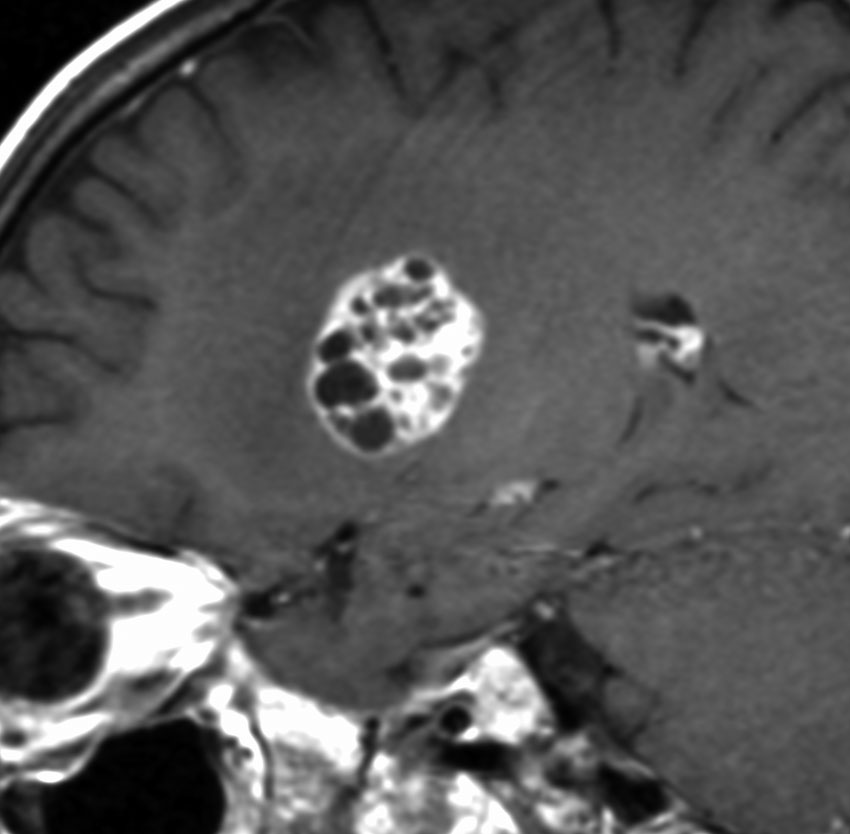

12歳の男児が尿崩症で発症しましたが,7ヶ月間診断がつかずに低ナトリウム血症による全身痙攣を生じました。下垂体と右被殻の2箇所に腫瘍があり,AFP 33ng/ml, HCG-beta 1.0mIUと上昇がみられました。神経下垂体の生検術でgerminomaの診断であったために化学療法が開始されました。CPA, VP-16, CDDP, VCRの併用化学療法に,MTXの髄腔内注入が2回でした。なぜこのような乱暴な化学療法を行なったのかは不明です。当然ですが,下垂体のgerminomaは左側のように消失しました。

でも化学療法中に,右大脳基底核にあった腫瘍が増大して,左のMRIのように脳浮腫も悪化しました。この時点で患者さんが転院してきました。腫瘍マーカーは陰転していて,どう見ても奇形腫が化学療法によるparadoxical responseを生じたものでした。ジャーミノーマが消えて奇形腫だけ増大するという現象です。

まず手術で全摘出して,成熟期奇形腫の病理診断を確定しました。それからICE化学療法を2コース加えて,脳脊髄照射 24Gy12分割を行いました。